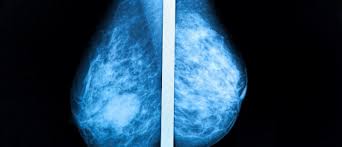

How Many Breast Cancers Are Found By Mammogram / Delayed Breast Cancer Diagnosis After Repeated Recall At Biennial Screening Mammography An Observational Follow Up Study From The Netherlands British Journal Of Cancer / The sensitivity of screening mammography in the united states is 72.4% to 80.1% 9,10;. The health professionals who take mammograms are called mammographers. Breast screening with a mammogram can help to find breast cancers early when they are too small to see or feel. It's rare for women to get cancer within a year of mammography, but it does. Overall, the sensitivity of mammography is about 87 percent 31 . For women age 40 to 49:

Detect slightly more cancers than a standard mammogram alone. After a mammogram that didn't show anything, and a sonogram that found the lump, i was diagnosed with stage 2 breast cancer. For example, they aren't 100% accurate in showing if a woman has breast cancer: Mammograms can also be used to check for breast cancer after a lump or other sign or symptom of the disease has been found. Breast screening with a mammogram can help to find breast cancers early when they are too small to see or feel.

Strategy For Lowering The Risk For Breast Cancer By Texas Breast Care Issuu from image.isu.pub Accuracy of mammograms mammography is good at finding breast cancer, especially in women ages 50 and older. Detect slightly more cancers than a standard mammogram alone. For example, they aren't 100% accurate in showing if a woman has breast cancer: And a female mammographer will usually take your mammogram. The current evidence suggests that breast screening reduces the number of deaths from breast cancer by about 1,300 a year in the uk. Mammograms miss about 15 percent of. Mammography women diagnosed with breast cancer after having yearly mammograms were diagnosed with cancers that were smaller and less advanced than women who had mammograms every 2 years, according to results from a small study. Mammograms are now known to be less reliable in women with dense breasts, which is.

Thus, approximately 20% to 28% of breast cancers are interval cancers. State that screening reduces breast cancer mortality by 20% or more, because it sounds more impressive than explaining that the absolute risk reduction is 1 in 1,000. It can find breast cancer when it is very small, even too small to feel. The current evidence suggests that breast screening reduces the number of deaths from breast cancer by about 1,300 a year in the uk. Mammograms can also be used to check for breast cancer after a lump or other sign or symptom of the disease has been found. Improve breast cancer detection in dense breast tissue. But a new study published in the new. This type of mammogram is called a diagnostic mammogram. The health professionals who take mammograms are called mammographers. Percent of women aged 40 and over who had a mammogram within the past 2 years: Not all breast cancers can be found on mammograms, especially in younger women who have more dense breast tissue. It is the best screening tool available today to find breast cancer early. The sensitivity of screening mammography in the united states is 72.4% to 80.1% 9,10;

Mammograms Why Early Detection Matters Houston Methodist On Health from www.houstonmethodist.org It is the best screening tool available today to find breast cancer early. Very early breast cancers are usually easier to treat, may need less treatment, and are more likely to be cured. The mammogram itself only takes a few minutes, but the appointment may last about 30 minutes. It can also detect calcifications Mammograms miss about 15 percent of. Breast screening with a mammogram can help to find breast cancers early when they are too small to see or feel. Studies indicate that combining a 3d mammogram with a standard mammogram can result in about one more breast cancer for every 1,000 women screened when compared with standard mammogram alone. It said 1 million women.

It said 1 million women. Little attention has been paid to how interval breast cancers are ultimately discovered. Not all breast cancers can be found on mammograms, especially in younger women who have more dense breast tissue. For women age 40 to 49: It can find breast cancer when it is very small, even too small to feel. Detect slightly more cancers than a standard mammogram alone. It's rare for women to get cancer within a year of mammography, but it does. Very early breast cancers are usually easier to treat, may need less treatment, and are more likely to be cured. Breast cancers found by screening are generally at an early stage. We estimate about 15 percent of breast cancers are diagnosed during a reasonable interval after a negative mammogram. The mammogram itself only takes a few minutes, but the appointment may last about 30 minutes. For example, they aren't 100% accurate in showing if a woman has breast cancer: Thus, approximately 20% to 28% of breast cancers are interval cancers.

Study Finds Google System Could Improve Breast Cancer Detection Voice Of America English from im-media.voltron.voanews.com For example, they aren't 100% accurate in showing if a woman has breast cancer: Improve breast cancer detection in dense breast tissue. If you have dense breast tissue, the odds of the cancer being missed on mammography start going up. But mammograms have their limits. The current evidence suggests that breast screening reduces the number of deaths from breast cancer by about 1,300 a year in the uk. The fda has now admitted that while mammography may be the best screening test to search for breast cancer, it does not find all breast cancer — especially in patients with high breast tissue density, which makes it harder to find breast cancer on a mammogram. Breast cancers found by screening are generally at an early stage. We estimate about 15 percent of breast cancers are diagnosed during a reasonable interval after a negative mammogram.

State that screening reduces breast cancer mortality by 20% or more, because it sounds more impressive than explaining that the absolute risk reduction is 1 in 1,000. For example, they aren't 100% accurate in showing if a woman has breast cancer: Breast cancers found by screening are generally at an early stage. Detect slightly more cancers than a standard mammogram alone. It's so important to listen to the messages our bodies are telling. For women age 40 to 49: Percent of women aged 40 and over who had a mammogram within the past 2 years: It can also detect calcifications Mammograms are the best breast cancer screening tests we have at this time. Overall, the sensitivity of mammography is about 87 percent 31 . And a female mammographer will usually take your mammogram. But mammograms have their limits. The current evidence suggests that breast screening reduces the number of deaths from breast cancer by about 1,300 a year in the uk.